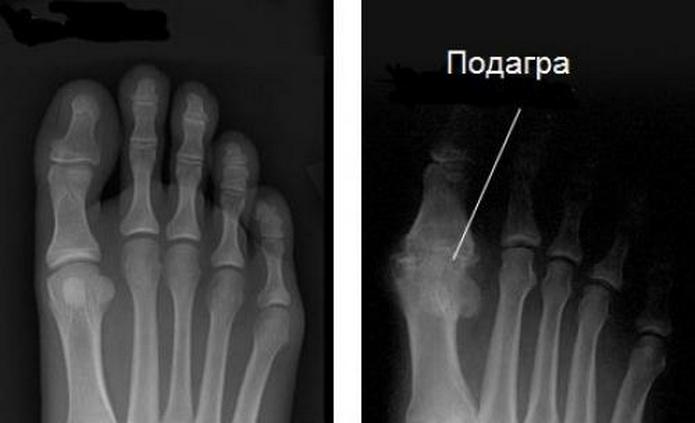

Термином «отложение солей в суставах» обозначают подагру с ее болезненными приступами. Для патологии характерно накопление в фалангах, локтях, голеностопах, коленях солей мочевой кислоты.

При повышении концентрации запускаются процессы кристаллизации с образованием мелких конкрементов-уратов. Они раздражают суставные структуры, провоцируют развитие острых или хронических воспалительных процессов. Рис при подагре полезен, но как часть лечебной диеты. Его употребление оказывает разноплановое действие на организм больного: